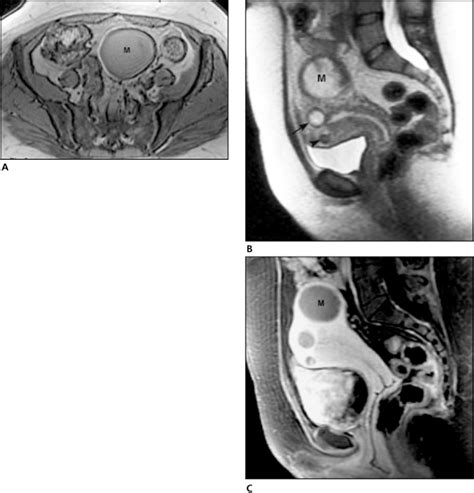

Diagnosing uterine myoma degeneration involves a combination of medical history, physical examination, and imaging tests. The diagnostic process typically includes:

• Imaging Tests: Ultrasound, MRI, or CT scans to visualize the fibroids and assess the extent of degeneration.